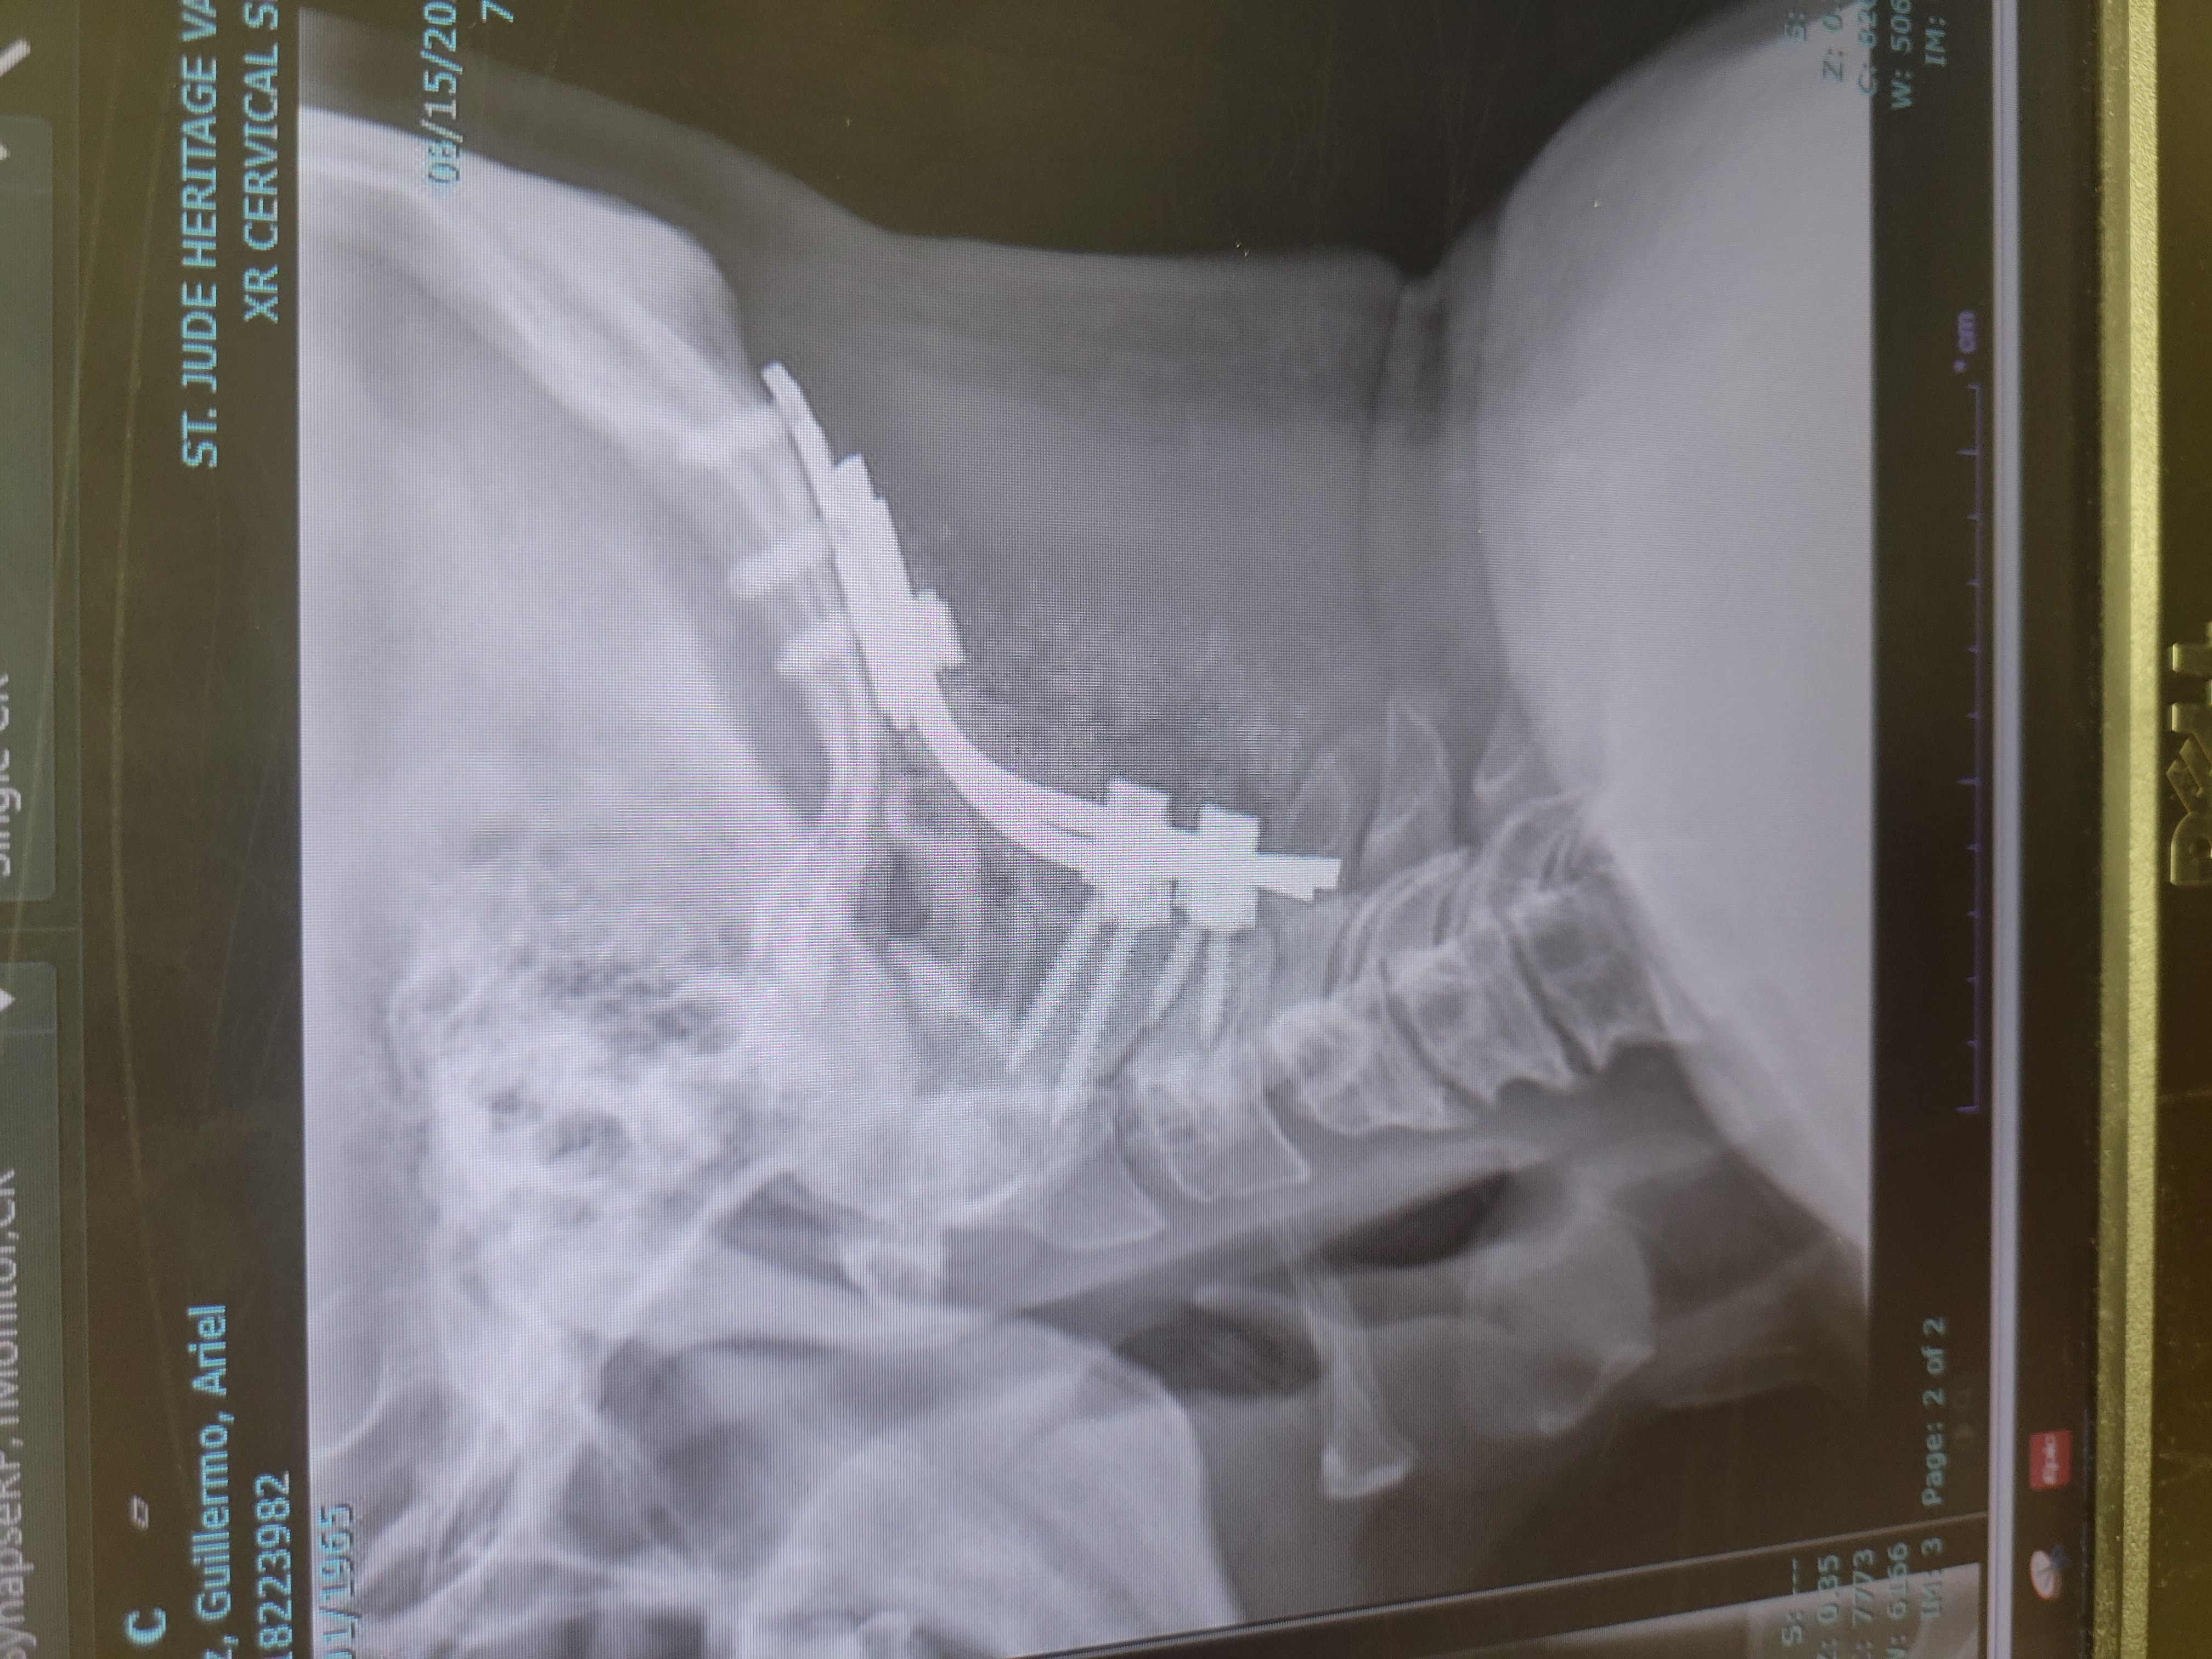

Great doctor, i broke my C1 after 4 months wearing a brace my c1 was worse, I spoke with him and I was ready for surgery he explain all the thing the can go wrong , I had surgery a moth after our meeting , Great hospital, great staff its been 8 moths and I feel great i was back in the gym 6 weeks after surgery.